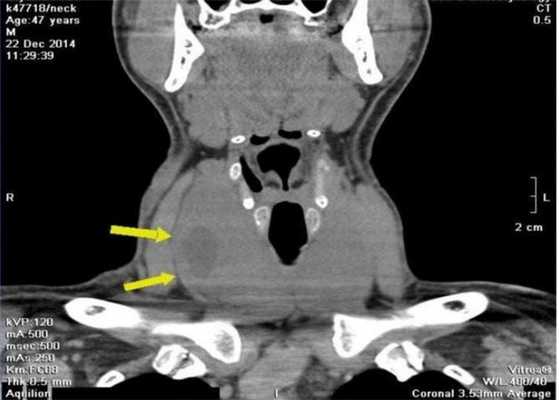

Узловой зоб щитовидной железы на компьютерной томограмме (очаговые изменения указаны стрелками)